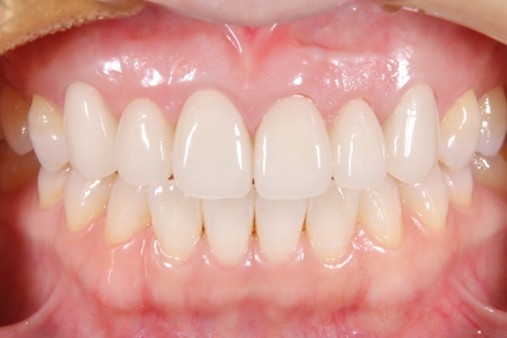

Before

6前歯の被せ物の歯肉が赤く腫れており膿が出ている部分もあった。審美的とは言えない状況

セラミック仮着時

After

セラミックセット後3年、歯肉の炎症はなく審美的な結果が得られている

初診時に入っていた被せ物は全て外し仮歯に置き換え、歯周基本治療を行った。その後歯肉の位置を調整して(クラウンレングスニング)仮歯を調整したのちにジルコニアセラミックを作成した。

審美修復に必要なことは、歯肉の健康だとつくづく感じている。いくら被せ物をセラミックで行ったところで土台である歯肉が健康でなければ本当の意味での審美修復は不可能であり長期的な予後が見込めない。まずは炎症のない口腔内の確立を第一に考える必要があると考える。